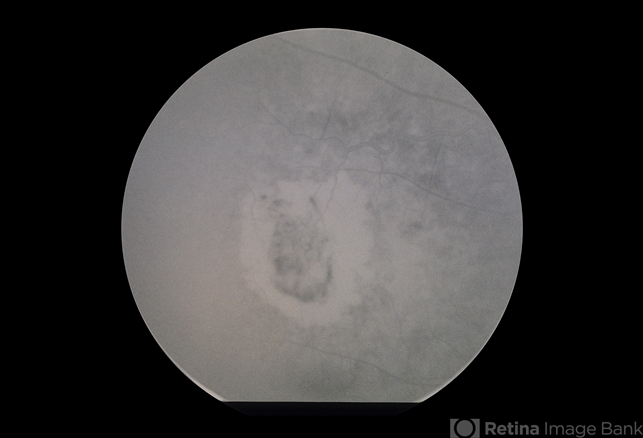

- AMD SRNVM with Hemorrhage

- subretinal neovascularization (SRNV), subretinal hemorrhage

- ARMD, SRNVM with sub retinal hemorrhage, 79-year-old white female, 20/300.